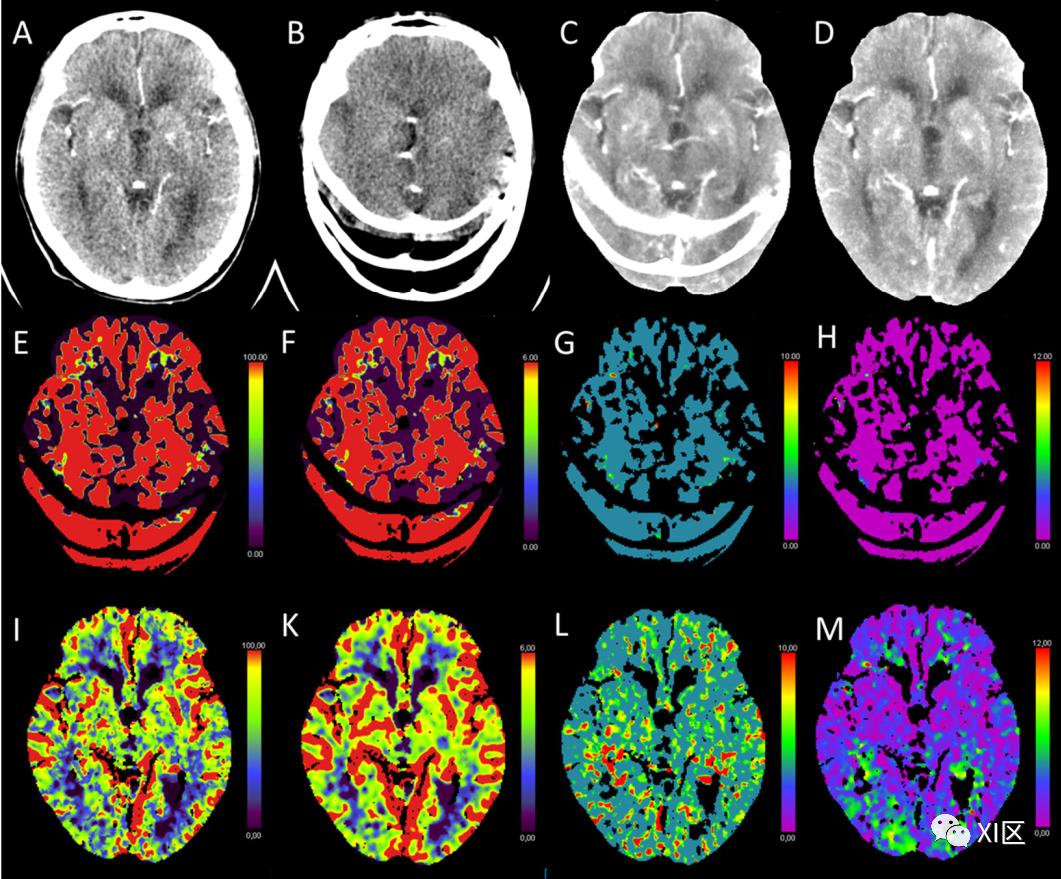

运动伪影、信噪比差或动脉和静脉输入功能不理想被描述为CTP最常见的技术陷阱。每个放射科医生都必须意识到这些问题和该模式的局限性。根据我们的临床经验,大多数缺陷已经被具有血管识别或运动校正等功能的自动后处理软件工具解决了。然而,有时也需要进行额外的人工后处理。图13概述了一个技术问题的例子,这个问题已经通过事后的人工修正得到解决。

图13 (A,B):不同时间点同一位置的大脑CTP。(C)自动后处理软件生成的CTP的最大密度投影(MIP),(D)手动后处理生成的CTP的MIP。(E-H):由自动后处理软件生成的CTP的彩色编码图:(E)脑血流量(CBF)[mL/100 g/min],(F)脑血容量(CBV)[mL/100 g],(G)平均通过时间(MTT)[s],和(H)Tmax [s]。(I-M):通过手动后处理从CTP生成的彩色编码图:(I)CBF[mL/100 g/min],(K)CBV[mL/100 g],(L)MTT[s],和(M)Tmax [s]。由于严重的运动伪影(B),自动后处理软件算法产生的灌注图在这个示例性的病人案例中不能用于诊断目的。在人工后处理步骤中,排除了有运动伪影的成像时间点。结果人工生成的灌注图(I-M)是可用的,显示出正常的脑灌注。4 结论